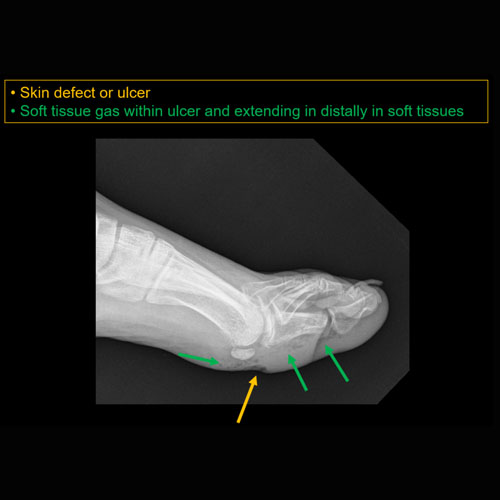

There is soft tissue ulceration. |

There is soft tissue gas. |